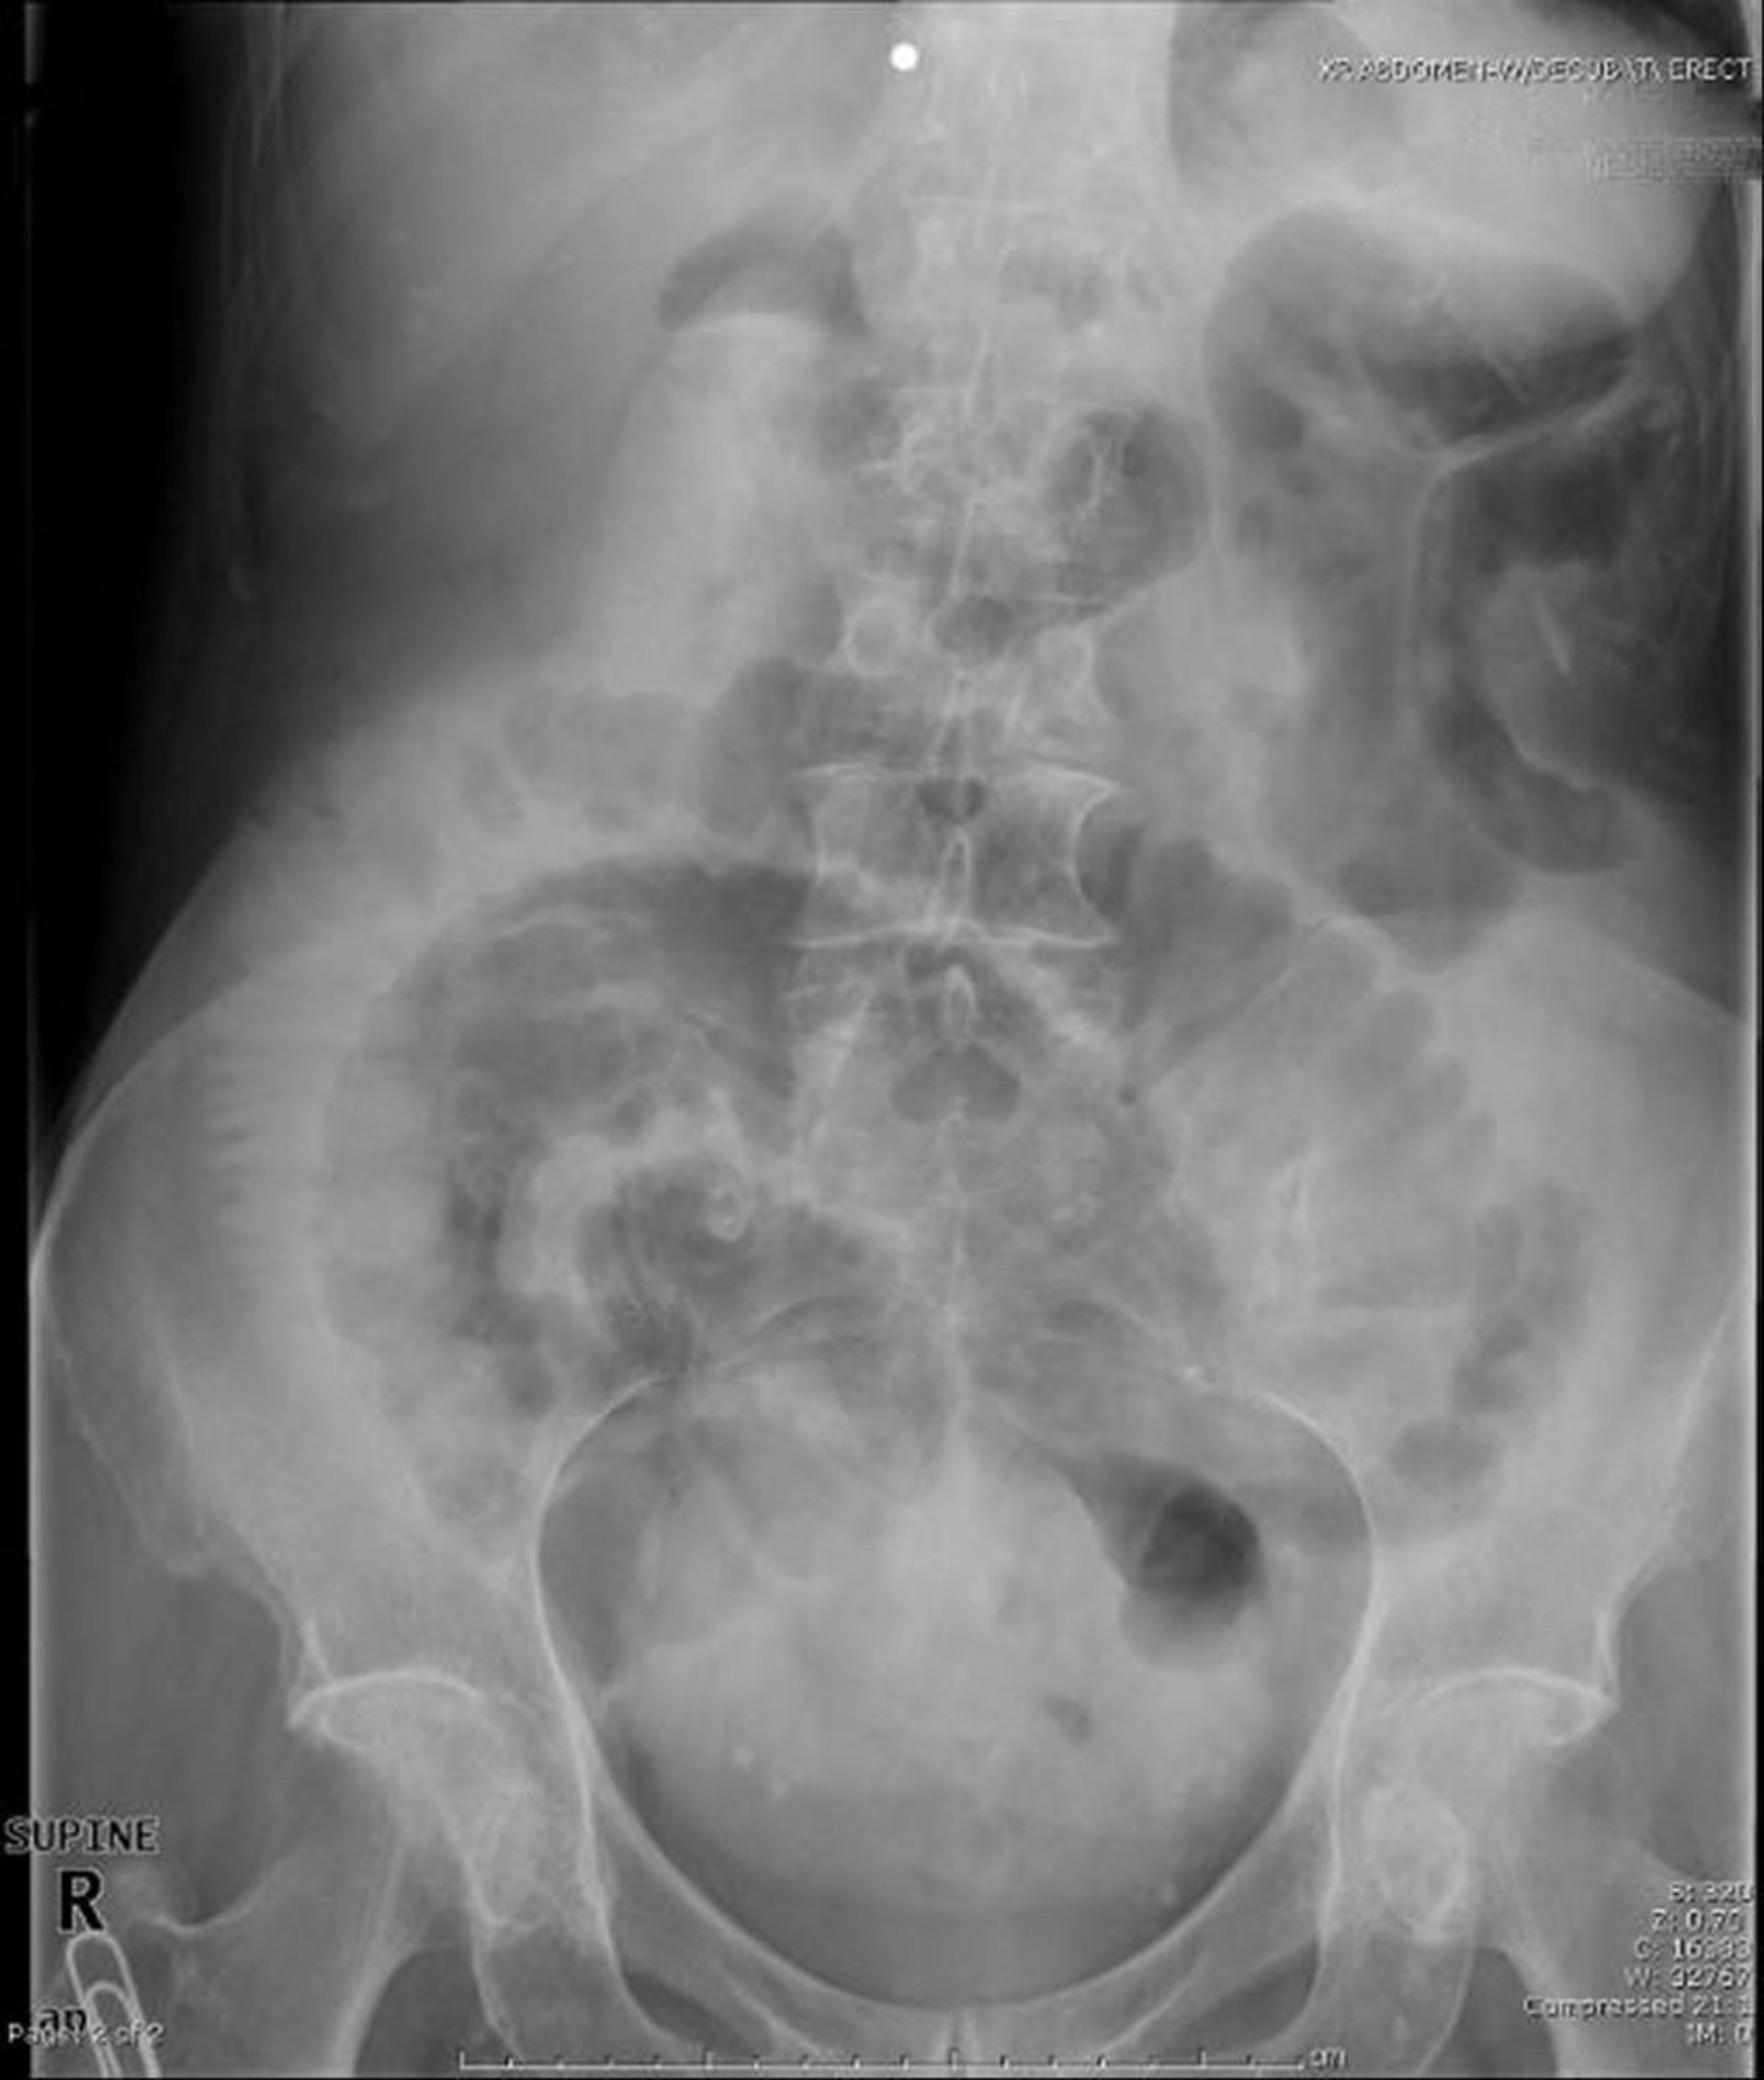

Тонкокишечная непроходимость (рентген в положении на спине)

Данная рентгенография органов брюшной полости в положении на спине указывает на непроходимость тонкого кишечника. Обратите внимание на расширенные петли тонкой кишки.

Image provided by Parswa Ansari, MD.